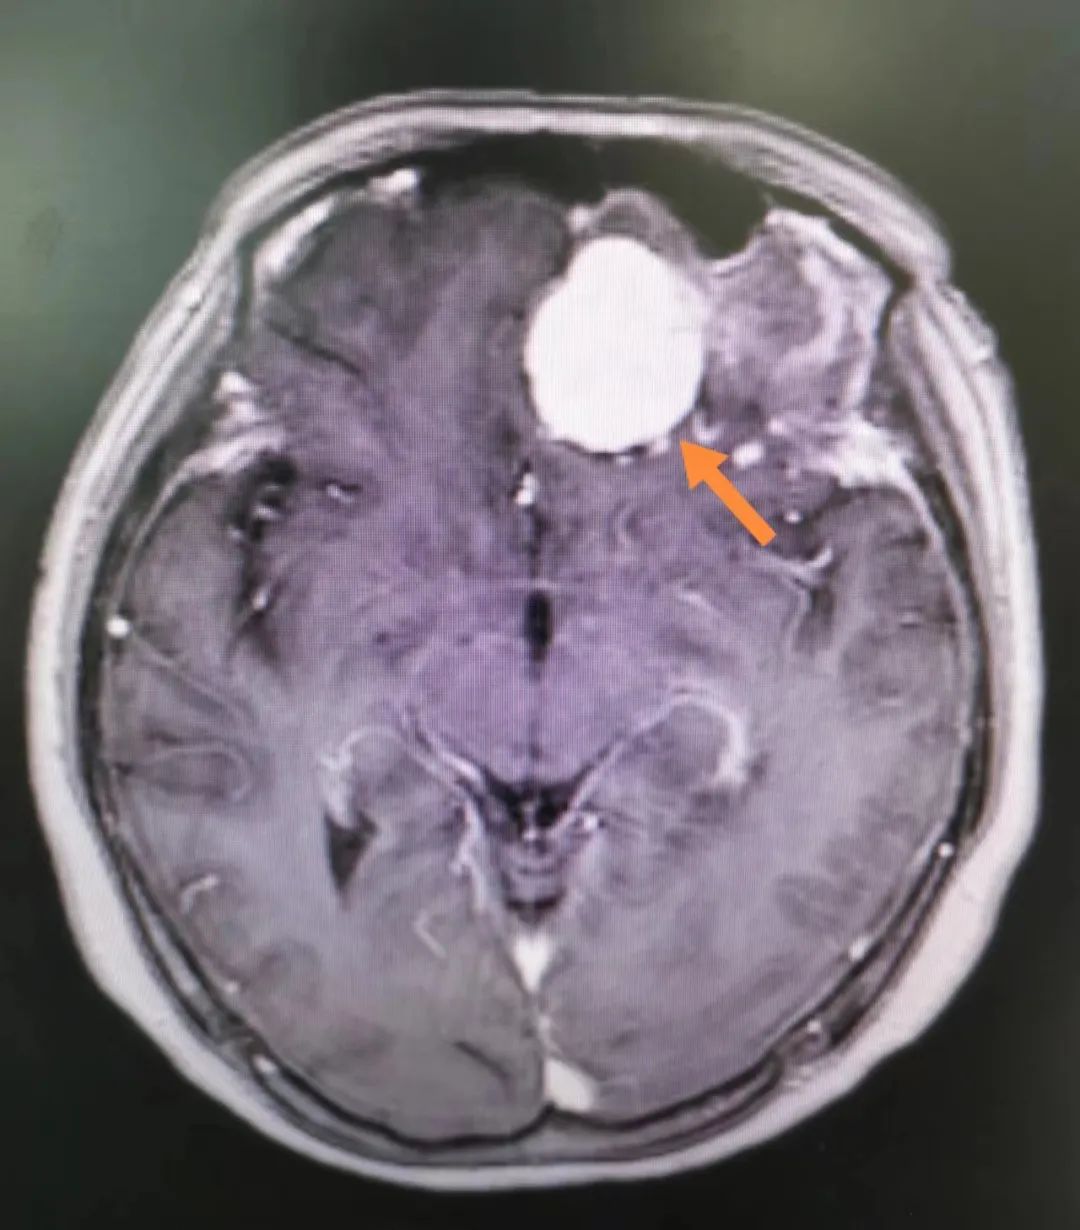

入院完善头部核磁共振检查发现,患者前颅底深处有一颗肉丸大小的肿瘤,考虑为良性的脑膜瘤。通过详细的术前讨论后,在神外一病区主任孙圣礼的指导下,王导导副主任医师、李义荣副主任医师、龚淑辉主治医师等,于8月19日在全麻下为其施行开颅肿瘤切除术。

术中发现,脑膜瘤紧临周围的嗅神经,操作稍有不慎就可能损伤神经。主刀医师借助显微镜小心翼翼一点一点地分离肿瘤。最终,手术历时4小时顺利完成。

“患者出现精神行为异常,是颅内肿瘤压迫额叶所致。”王导导副主任医师表示,额叶是人体大脑重要的组成部分,主管精神、情感、行为、记忆、理解、运动、语言等。当额叶受压或损伤,患者可出现相对应的功能症状,如记忆力减退、反应迟缓、行走不稳、精神行为异常等。他提醒,一旦身边人突然出现精神行为异常,应及时前往正规医院查明病因,以免延误治疗。